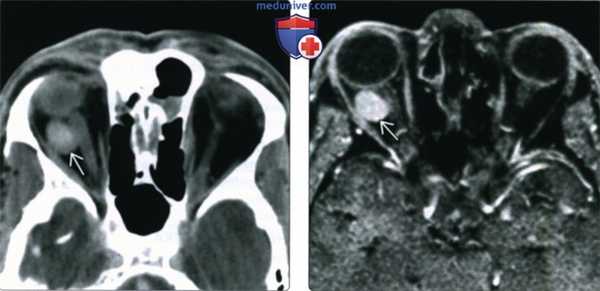

(Слева) При КТ с КУ в аксиальной проекции в правой глазнице в жировой клетчатке внутри мышечного конуса определяется овоидное контрастное объемное образование с четкими контурами, прилегающее к зрительному нерву и наружной прямой мышце.

(Справа) При МРТ Т1ВИ FS с КУ в аксиальной проекции наблюдается интенсивное контрастирование интраконального объемного образования. Образование имеет относительно небольшие размеры, оказывает незначительный эффект объемный эффект и не имеет агрессивных признаков. Такие образования зачастую существуют бессимптомно или вызывают постепенные изменения, не замечаемые пациентом.